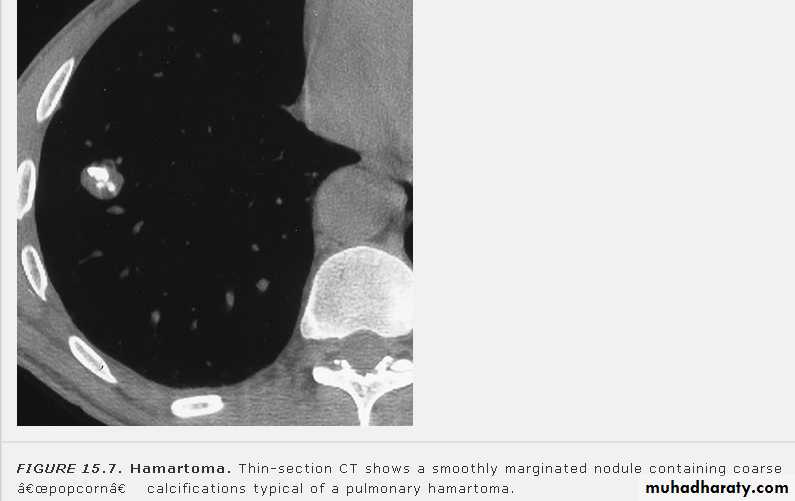

CAVITARY LESIONS

Abscess: necrosis of lung parenchyma +\-

bronchial communication

Fungus ball (air crescent sign)

Ruptured hydatid cyst (water lily sign)

Pneumatoceles due to air leak into

pulmonary interstitium (S. aureus)